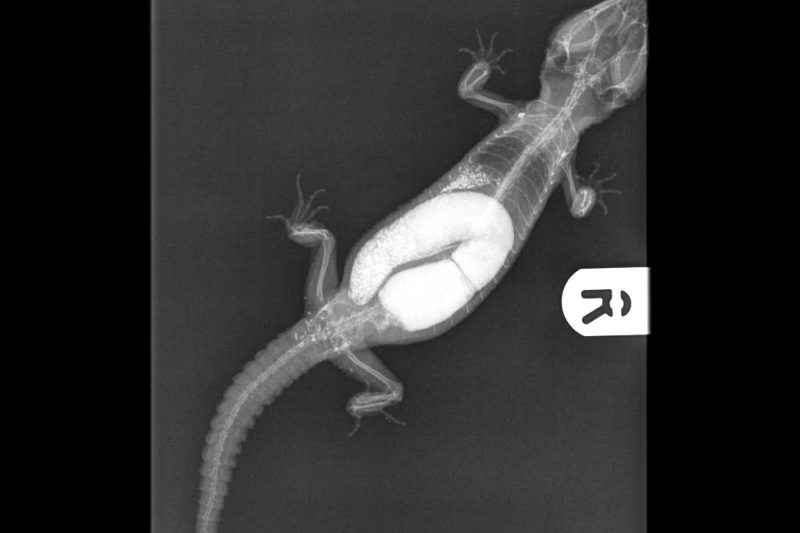

Reptiles have an amazing system which removes water from waste in the intestine as it travels – all animals do, but in desert living creatures it’s highly developed. If waste sits in the system for a long time the moisture continues to be removed until you are left with an object that resembles a stone blocking the gut. It’s called a ‘fecalith’, and is basically a stone made of dried, hardened poo. The only solution for this condition is surgery to remove it, so it’s very important to keep your reptile hydrated.

Foreign object obstruction comes when an animal eats something totally inappropriate, and it gets stuck either in the stomach or intestine. Coins, elastic bands, batteries, items of clothing, pieces of paper, hair bands – some animals have an insatiable curiosity as to the taste of strange objects, and the result can be a very expensive trip to the vets. If you think your pet has eaten something unsuitable, take it to the vets as soon as possible. And make sure they don’t have repeat access to that sort of item again!

Suspected infections, neurological disorders and tumours should be seen as soon as possible by a reptile experienced vet. In fact, any lumps, bumps, suspicious bulges, lack of defecation – ANYTHING – that causes you concern should be checked by a vet. If your animal is worrying you for any reason at all, then you should take it to a vet without delay.